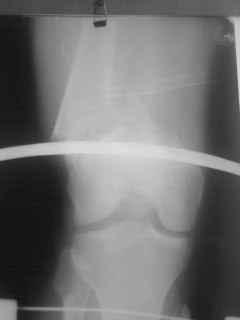

01.12.09г. оперировал больного с подобной травмой в ЦРБ на 4-е сутки после ДТП. Перелом открытый - рана находилась медиально чуть выше надколенника длиной примерно 3-4 см. До этого при поступлении было выполнено ПХО раны и скелетное вытяжение. На момент операции рана без признаков воспаления, состояние больного удовлетворительное.На первичных снимках перелом А3. На операции оказалось С3. Перелом фиксирован мыщелковой пластиной. Для репозиции понадобился медиальный доступ. Медиальный блок дополнен костно-губчатым аутотрансплантатом. На сегодняшний день раны заживают первично, швы еще не сняты, температура тела нормальная, отек бедра значительно уменьшился, имеется анемия средней степени, проводится ЛФК. Фото досылаю

Чем остеосинтез аппаратом в этом конкретном случае был бы предпочтительнее - и менее инвазивно, и пластику бы не надо было делать, и ось можно было бы лучше контролировать, включая послеоперационный период. А сейчас варусный коллапс градусов 15, и для исправления оси потребуется отдельная операция...

о дальнейшей тактике лечения можно думать после четких проекций: на надколенник, профиль, осевой снимок нижней конечности. patella baja, УВО - может чисто проекционное? В плане пластики, по-моему, рекомендовано уже у МЕМ.